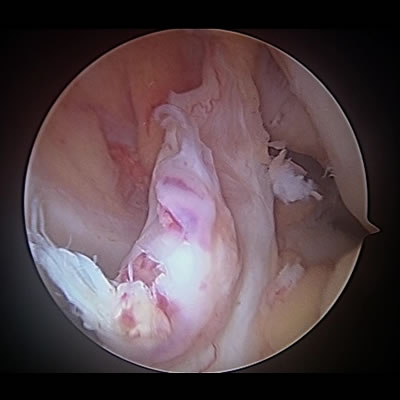

肩関節唇形成術(反復性肩関節脱臼)

関節鏡で肩関節の中を確認し、細い処置具や糸の着いたアンカーを使って、剥がれた骨や関節唇(靱帯)を元の状態に修復します。

ラグビーなどのコンタクトスポーツで大きな外力が加わることがあらかじめ予測される場合は、元の状態に戻すだけでは不十分と考え、肩関節の前方にある烏口突起という骨を肩関節に移植するBristow法といわれる処置を追加し、肩関節を補強します。